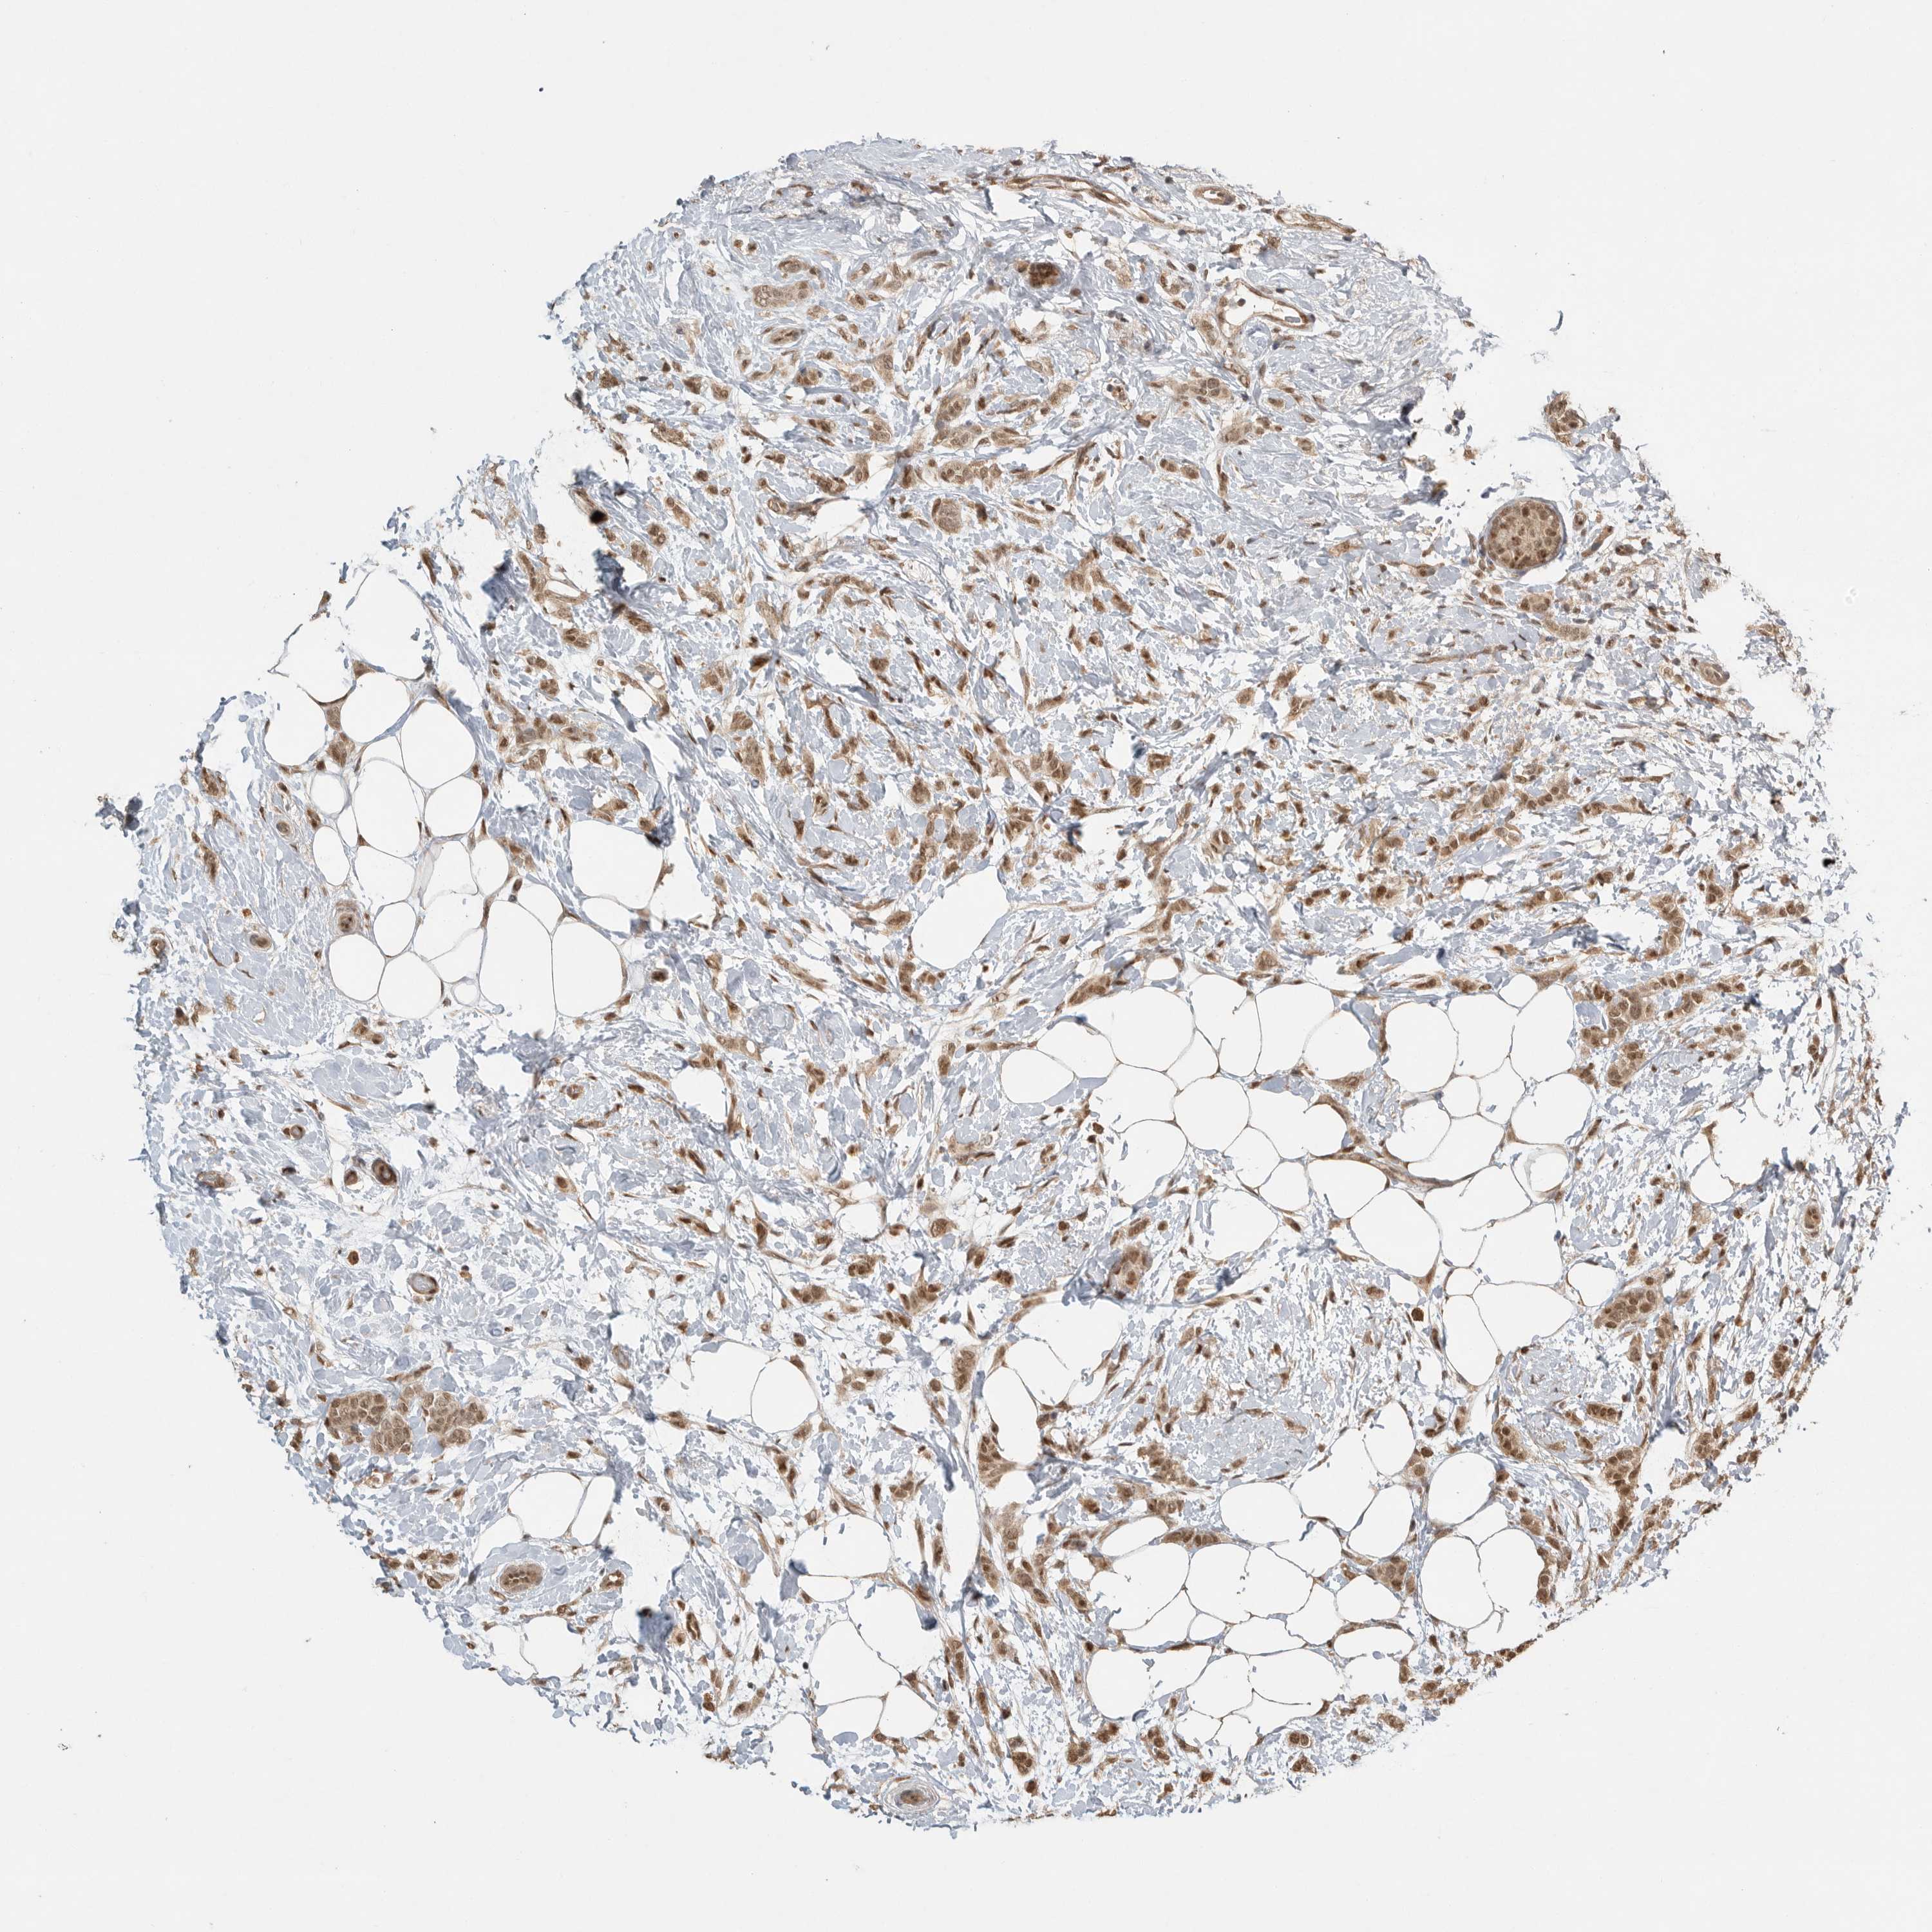

CANCER BREAST CANCER Show tissue menu

BRCA TCGA BRCA VALIDATION PROTEIN EXPRESSION